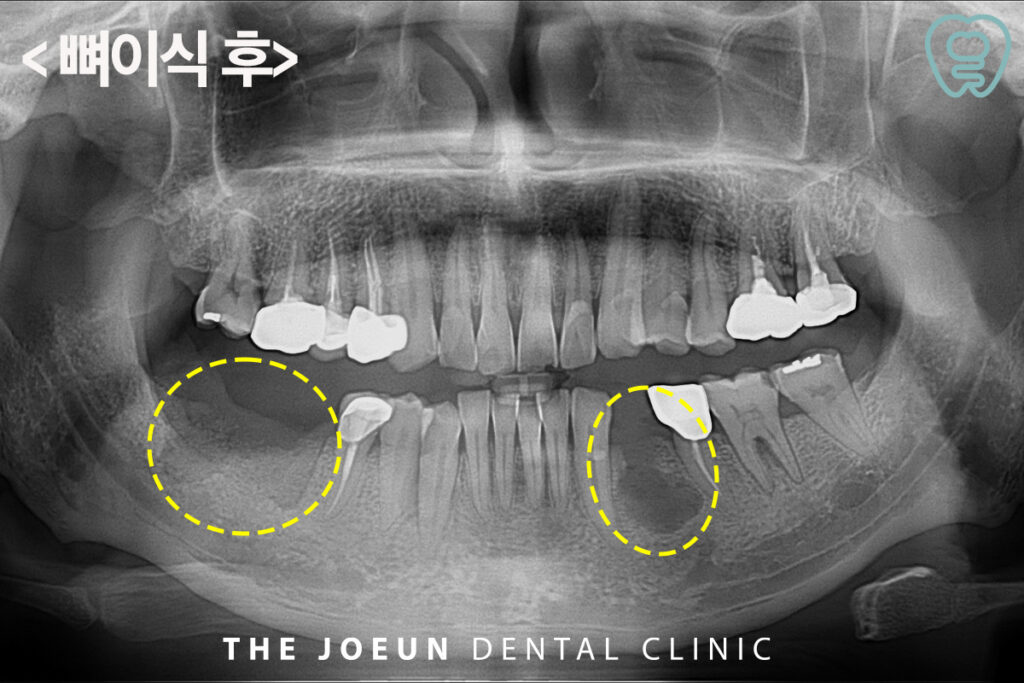

원인이 되는 치아들을 발치한 후 뼈이식을 먼저 진행하였습니다.

잇몸뼈의 부족은 임플란트 치료 전 3D CT 촬영 등의 정밀 검사를 통해서도 알 수 있는데요. 잇몸뼈의 상태에 따라 적절한 뼈이식 방법을 선택하고 환자의 구강 구조를 고려한 맞춤형 치료 계획을 세워야 합니다. 또한, 수술 후 철저한 구강 관리와 정기적인 검진을 통해 임플란트가 오랫동안 유지될 수 있도록 해야 하는데 이식된 조직이 안정화되기까지 수개월의 시간이 필요하므로 이 기간 동안 환자분께서는 금연, 금주, 철저한 구강 위생 관리 등을 통해 치유를 도와야 합니다.